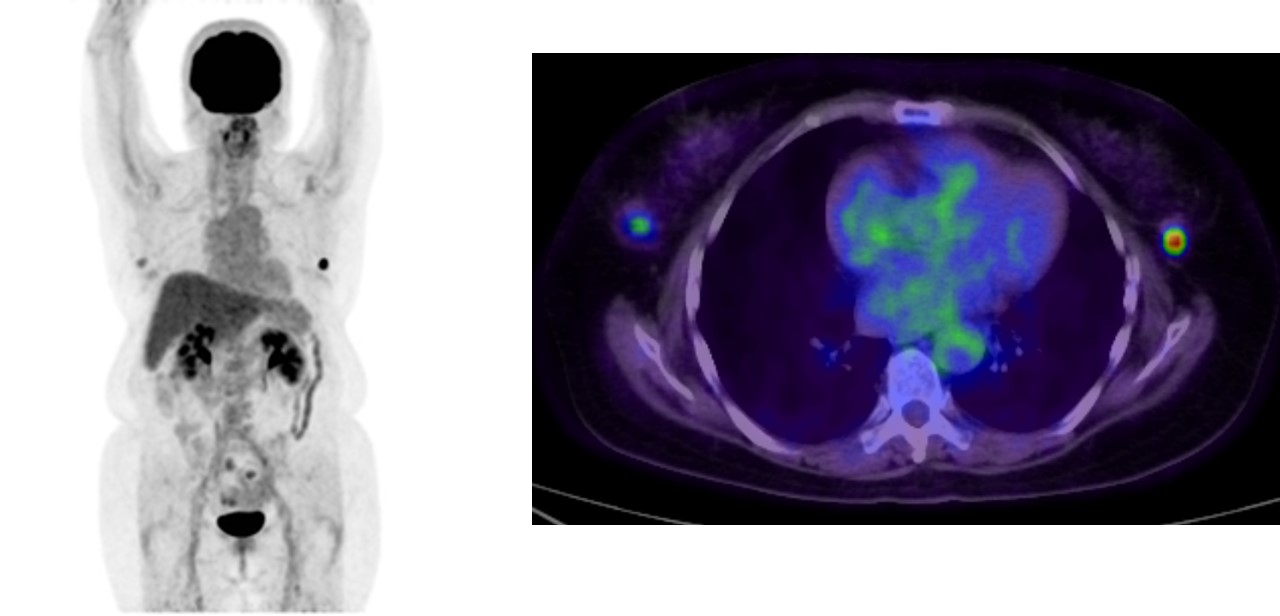

FDG-PETでは、右腫瘤は弱い集積、左腫瘤は強い集積。